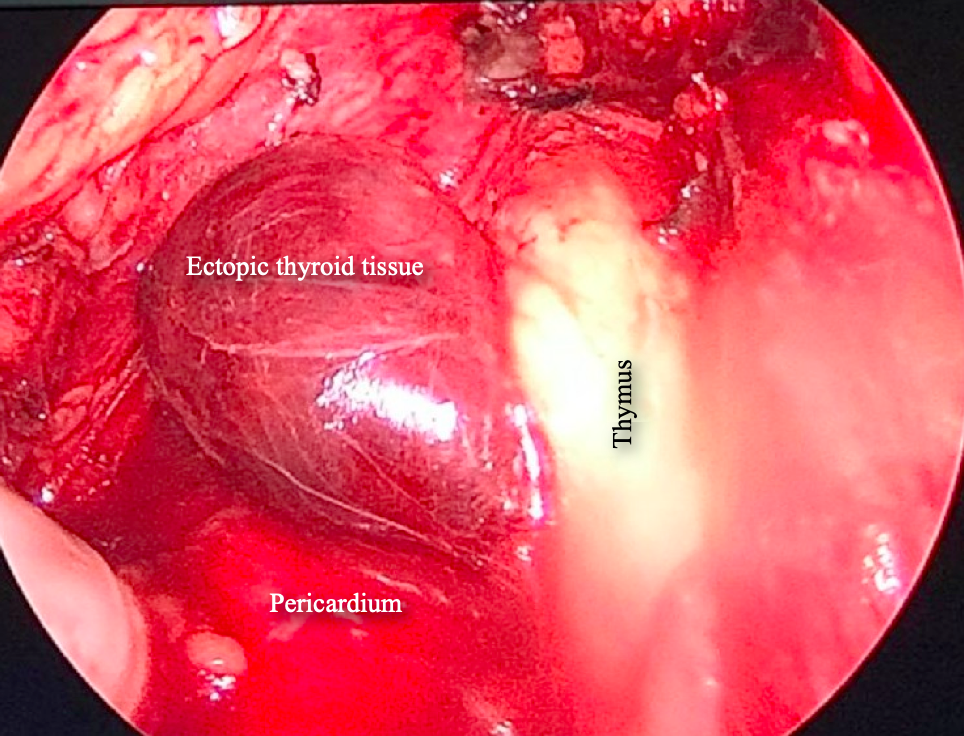

Figure 4. Videothoracoscopic view of the anterior mediastinum showing the dark red mass on the left side. No major feeding vessel was identified.

Intraoperative frozen section showed that the mediastinal lesion was not a thymoma but an ectopic thyroid gland (Figure 6A). Hematoxylin and eosin staining confirmed the diagnosis and depicted a normal thyroid tissue, no features of malignancy were identified. No thyroid tissue was found in the involuted thymus (Figure 6B).